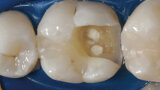

Aplikace MTA s použitím Produit Dentaires (PD) MAP System